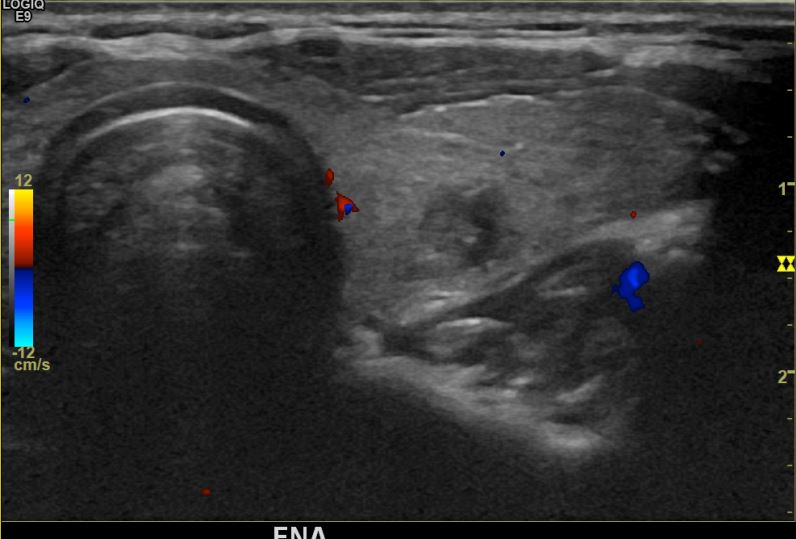

상기환자 외부검진이후경과관찰위해  내원하신 30대후반 여성분으로 의심스러운우엽혹 세포검사진행후 갑상선암으로 진단되었습니다